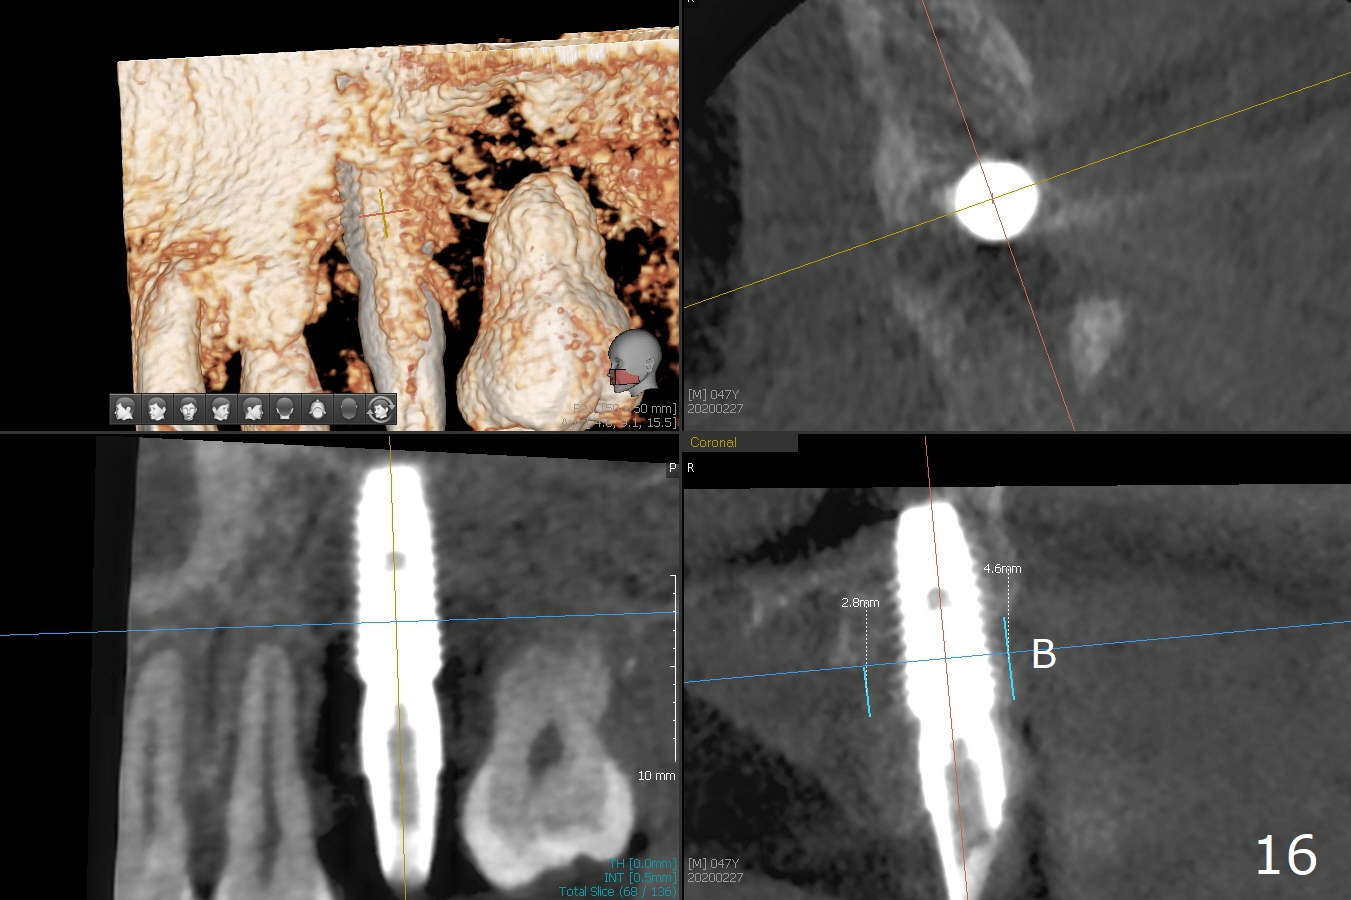

After debride-ment, use of Round Brush, buccal plate decorti-cation and abutment retigh-tening, sticky bone is placed around the exposure implant (I) threads and abutment (A) cuff amply (Fig.1 (3D image: buccal view) *), as compared to preop CT in Fig.16.